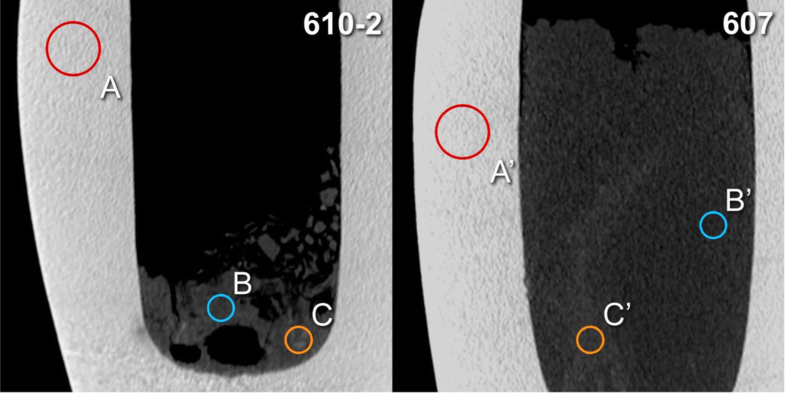

CT-based density measurements. Placement of regions of interest A and A' (calcite mineral), B and B′ (surrounding material) and C and C′ (structures of higher radiodensity) for two canopic jars (inventory numbers 610-2 and 607) on sagittal multiplanar reconstructions (slab thickness 1.5 mm)

CT-based density measurements (HU)

| Canopic jar inventory number | ROI A, calcite, diameter 20 mm Mean ± SD (range) | ROI B, surrounding material, diameter 10 mm Mean ± SD (range) | ROI C, putative tissue structures, diameter 10 mm Mean ± SD (range) |

|---|---|---|---|

| 607 | 2158±176 (1607–2789) | 186±90 (−88–448) | 344 ± 92 (71–595) |

| 610-2 | 2221±185 (1469–2823) | 224±69 (38–455) | 351 ± 150 (−16–790 |

| 617 | 2139±160 (1357–2653) | 216±106 (−120–472) | 373 ± 105 (−2–664) |

| 622-1 | 2342±108 (2059–2763) | 207±69 (−101–347) | 309 ± 67 (−16–507) |

| Mean | 2215±160 (1623–2757) | 208±85 (−68–431) | 344 ± 108 (9–639) |